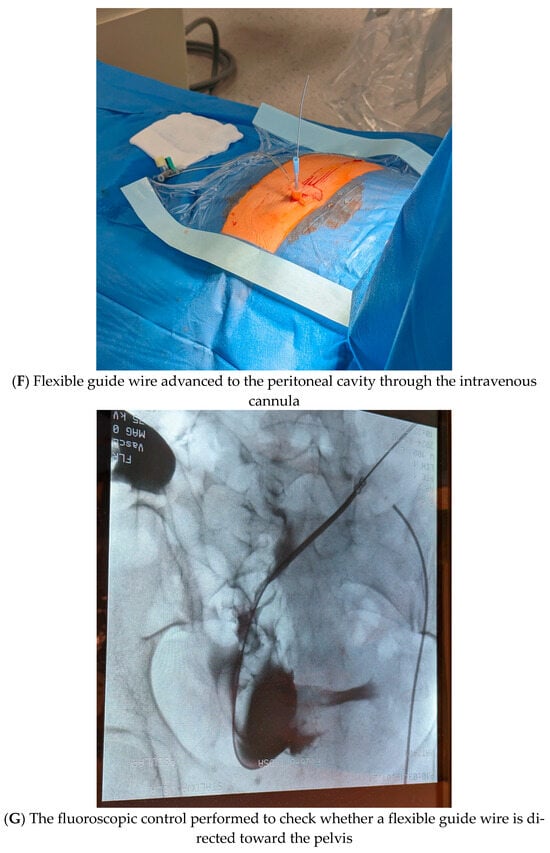

- Once peritoneal cavity access was achieved, a flexible guide wire was advanced through the intravenous cannula (Figure 1F). Next, the fluoroscopic control was performed to check whether a flexible guide wire was directed toward the pelvis (Figure 1G). If yes, the intravenous catheter was replaced, and a dilator and the peel-away sheath (Argyle–Peritoneal Dialysis Catheter Kit, Covidien, Mansfield, MA, USA) were advanced over the wire into the abdominal cavity (Figure 1H). Next, a guide wire as well as the introducer of the peel-away sheath were removed, leaving the tubing in the abdomen.